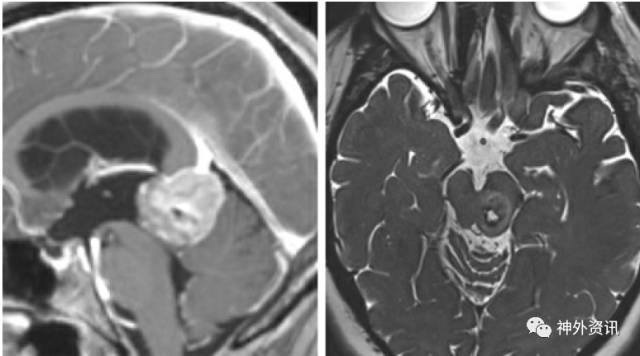

图1. 相对于中线入路,旁正中小脑上入路有许多优势: 1) 颅骨切开术多数不会威胁到优势侧(右侧)横窦和窦汇,更微创;2) 只经过一侧小脑半球进行操作;3) 通常情况小脑蚓部桥静脉受到保护;4) 经小脑外侧的视线斜度更小,为显露肿瘤下极提供较清晰的视线。再次手术可以通过对侧的小脑上入路完成。旁正中或者中线入路可以显露第三脑室后部肿瘤(下图)。

图2. 松果体区(左图)及中脑后外侧(右图)大型病变可以很容易通过小脑上入路显露。